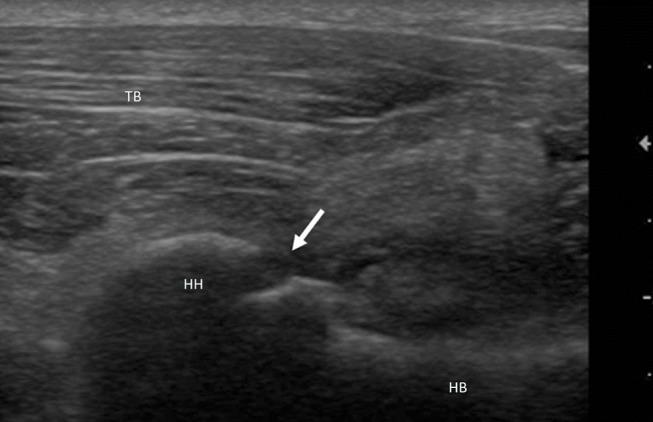

犬肩部跛行:超声检查、征候及血液生化检查结果相关性的初步调查

Forelimb lameness in medium and large breed dogs is frequently caused by traumatic or degenerative injuries of the shoulder. Patient history, physical examination, x-rays, blood, and chemical work are routinely used to achieve diagnosis, and may be associated with ultrasonography or magnetic resonance imaging. Ultrasonography is increasingly popular in small animal practice due to its low cost, ease of repetition, and the fact that it is non-invasive and can be performed in conscious patients. It is also widely accepted that muscular stress or injuries can induce detectable variations in blood and chemical work. The aim of this preliminary study is to search for correlation between measurements of selected hematobiochemical parameters and ultrasound diagnosis in dogs affected by shoulder injuries. A retrospective study was conducted on orthopedic clinical records of dogs presented to our Veterinary Teaching Hospital for lameness caused by shoulder problems over a period of 5 years. Dogs with both hematobiochemical and ultrasound examinations were selected. Patients were classified into 5 groups according to ultrasound diagnosis: (1) mild/moderate tendinopathy, (2) severe tendinopathy, (3) articular damage, (4) chronic myopathy, and (5) neoplastic injury. Statistical analysis was performed to detect possible correlations between group and hematobiochemical parameters. Forty-four dogs met the inclusion criteria and forty-nine shoulders were diagnosed as injured. Significant differences were found between the age, sex, body weight, neutrophil count, and AST levels. In particular, statistically significant increases were found for neutrophil count and AST concentration in case of ultrasonographically diagnosed severe tendinopathy, articular damage, and neoplastic pathology. Further and wider studies are suggested to determine whether these biomarkers can become a useful diagnostic aid.

中大型犬的前肢跛行通常由肩部的创伤性或退行性损伤引起。患者病史、体格检查、X光、血液和化学检查通常用于进行诊断,可能还会结合超声检查或磁共振成像。超声检查因其成本低、易于重复,且具有非侵入性且可在清醒患者身上进行的特点,在小动物临床实践中越来越受欢迎。人们也普遍认为,肌肉压力或损伤会在血液和化学检查中引起可检测到的变化。这项初步研究的目的是寻找受肩部损伤影响的犬只中选定血液生化参数测量值与超声诊断之间的相关性。对在5年期间因肩部问题导致跛行而被送到我们兽医教学医院的犬只的骨科临床记录进行了回顾性研究。选择了同时进行了血液生化和超声检查的犬只。根据超声诊断将患者分为5组:(1) 轻度/中度肌腱病,(2) 重度肌腱病,(3) 关节损伤,(4) 慢性肌病,(5) 肿瘤性损伤。进行了统计分析以检测组与血液生化参数之间可能的相关性。44只犬符合纳入标准,49个肩部被诊断为受伤。在年龄、性别、体重、中性粒细胞计数和AST水平之间发现了显著差异。特别是,在超声诊断为重度肌腱病、关节损伤和肿瘤性病变的情况下,中性粒细胞计数和AST浓度在统计学上有显著升高。建议进行进一步更广泛的研究,以确定这些生物标志物是否可以成为有用的诊断辅助手段。